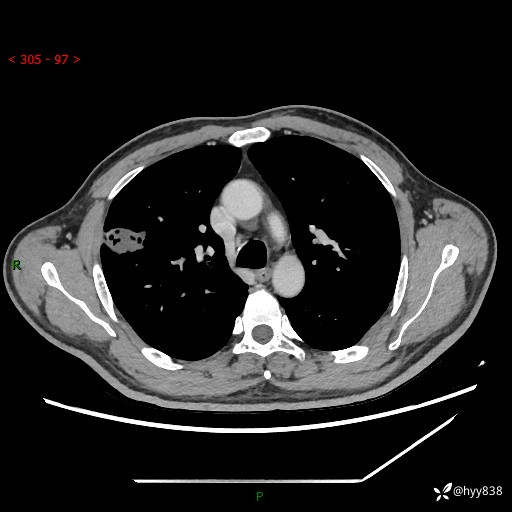

现病史:患者2天前体检完善胸部CT提示:右上肺团块影,炎症可能,肿瘤性病变不除外,冠状动脉钙化,无咳嗽、咳痰,无寒战发热,无恶心、呕吐等其他特殊不适,未予以特殊治疗,现为明确病变性质来我院就诊,门诊以“肺肿物性质待查”收入我科。 起病以来,患者精神、饮食、睡眠可,大小便正常,体力体重较前无明显变化。

胸部CT平扫+增强